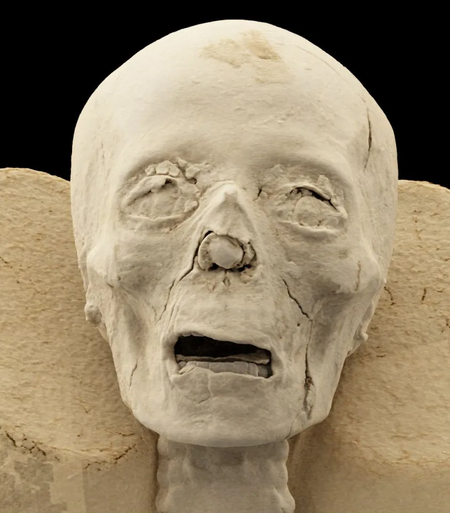

Các nhà khoa học đã hé lộ những chi tiết rùng rợn về các bộ phận cơ thể của một xác ướp Ai Cập cổ đại mà bạn chưa từng thấy trước đây.

Công nghệ quét hình ảnh tiên tiến đã hé lộ mọi thứ, từ hộp sọ đến một bàn chân được bảo quản tốt với một phần lớn bị mất ở ngón chân cái.

Các chuyên gia đã xem xét hai hộp sọ với độ chi tiết đáng kinh ngạc.

Việc cố gắng nhìn xuyên qua các lớp bao bọc xác ướp mà không làm hư hại chúng là một thách thức lớn đối với các nhà khoa học.

Mục đích chính của nghiên cứu là xem xét cấu trúc bên trong của các bộ phận cơ thể để tìm kiếm các dấu hiệu bất thường và hiểu rõ hơn về các kỹ thuật bảo quản bí ẩn mà người Ai Cập cổ đại đã sử dụng.

Nhìn chung, họ đã xem xét hai đầu, hai chi dưới bên trái, một bàn chân và một bàn tay.

“Trước đây, các di hài đã được một nhóm nghiên cứu kiểm tra, nhưng những hình ảnh hiện tại cung cấp cái nhìn chi tiết hơn bao giờ hết và dự kiến sẽ mang lại những phát hiện mới, có giá trị khoa học về các di hài đã được bảo quản trong bộ sưu tập hàng thập kỷ”, Krisztina Scheffer, Trưởng phòng Bảo tàng Lịch sử Y học MNMKK Semmelweis cho biết .

“Dựa trên những kết quả thu được cho đến nay, rõ ràng là công nghệ hình ảnh hiện đại mở ra những triển vọng mới trong nghiên cứu về xác ướp,” Scheffer nói thêm.

“Nó có thể hé lộ thông tin ẩn giấu trong những hiện vật có niên đại hàng nghìn năm mà không làm hư hại chúng.”

Các chuyên gia đã xem xét hai hộp sọ với độ chi tiết đáng kinh ngạc.

Công nghệ tiên tiến nhất đã được sử dụng để hé lộ thêm nhiều chi tiết về các xác ướp.

Việc cố gắng nhìn xuyên qua các lớp bao bọc xác ướp mà không làm hư hại chúng là một thách thức lớn đối với các nhà khoa học.

Mục đích chính của nghiên cứu là xem xét cấu trúc bên trong của các bộ phận cơ thể để tìm kiếm các dấu hiệu bất thường và hiểu rõ hơn về các kỹ thuật bảo quản bí ẩn mà người Ai Cập cổ đại đã sử dụng.

Nhìn chung, họ đã xem xét hai đầu, hai chi dưới bên trái, một bàn chân và một bàn tay.

“Trước đây, các di hài đã được một nhóm nghiên cứu kiểm tra, nhưng những hình ảnh hiện tại cung cấp cái nhìn chi tiết hơn bao giờ hết và dự kiến sẽ mang lại những phát hiện mới, có giá trị khoa học về các di hài đã được bảo quản trong bộ sưu tập hàng thập kỷ”, Krisztina Scheffer, Trưởng phòng Bảo tàng Lịch sử Y học MNMKK Semmelweis cho biết .

“Dựa trên những kết quả thu được cho đến nay, rõ ràng là công nghệ hình ảnh hiện đại mở ra những triển vọng mới trong nghiên cứu về xác ướp,” Scheffer nói thêm.

“Nó có thể hé lộ thông tin ẩn giấu trong những hiện vật có niên đại hàng nghìn năm mà không làm hư hại chúng.”